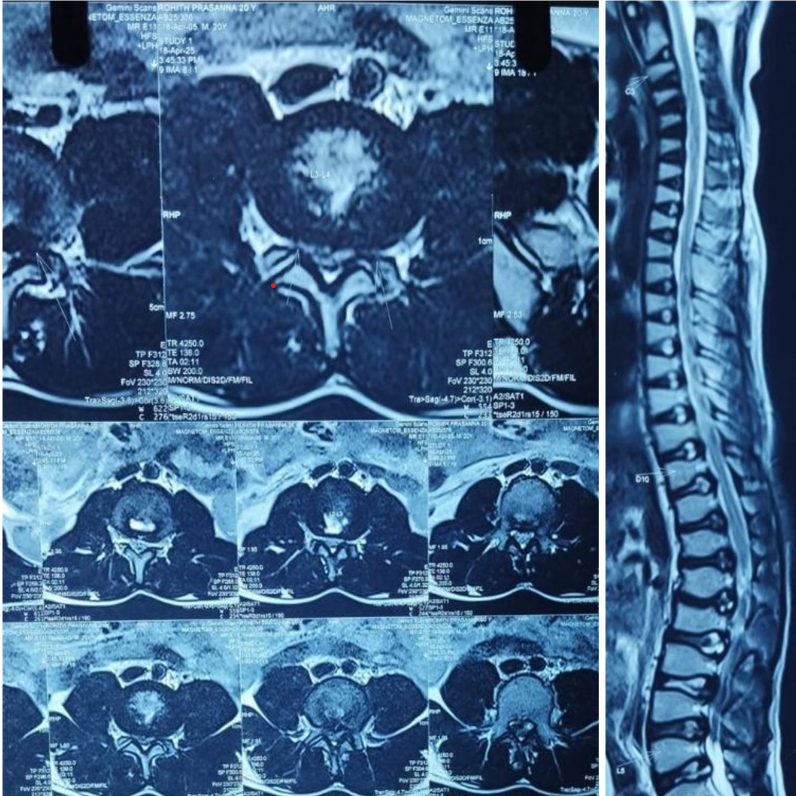

Radiological evaluation included plain radiographs, which showed reduced interpedicular distance and short pedicles in the lumbar spine, consistent with congenital canal stenosis (Fig. 2). Computed tomography confirmed the presence of short pedicles without evidence of ossified ligamentum flavum (Fig. 3). Magnetic resonance imaging demonstrated multilevel lumbar stenosis from L1 to L5 with thickened ligamentum flavum. Pre-operative Oswestry disability index score was 60%. Routine laboratory investigations were within normal limits.

Figure 3: Magnetic resonance imaging axial and sagittal T2W images showing lumber canal stenosis L1–L5.